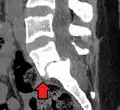

![]() | |

| X-ray of the lateral lumbar spine with a grade III anterolisthesis at the L5-S1 level | |